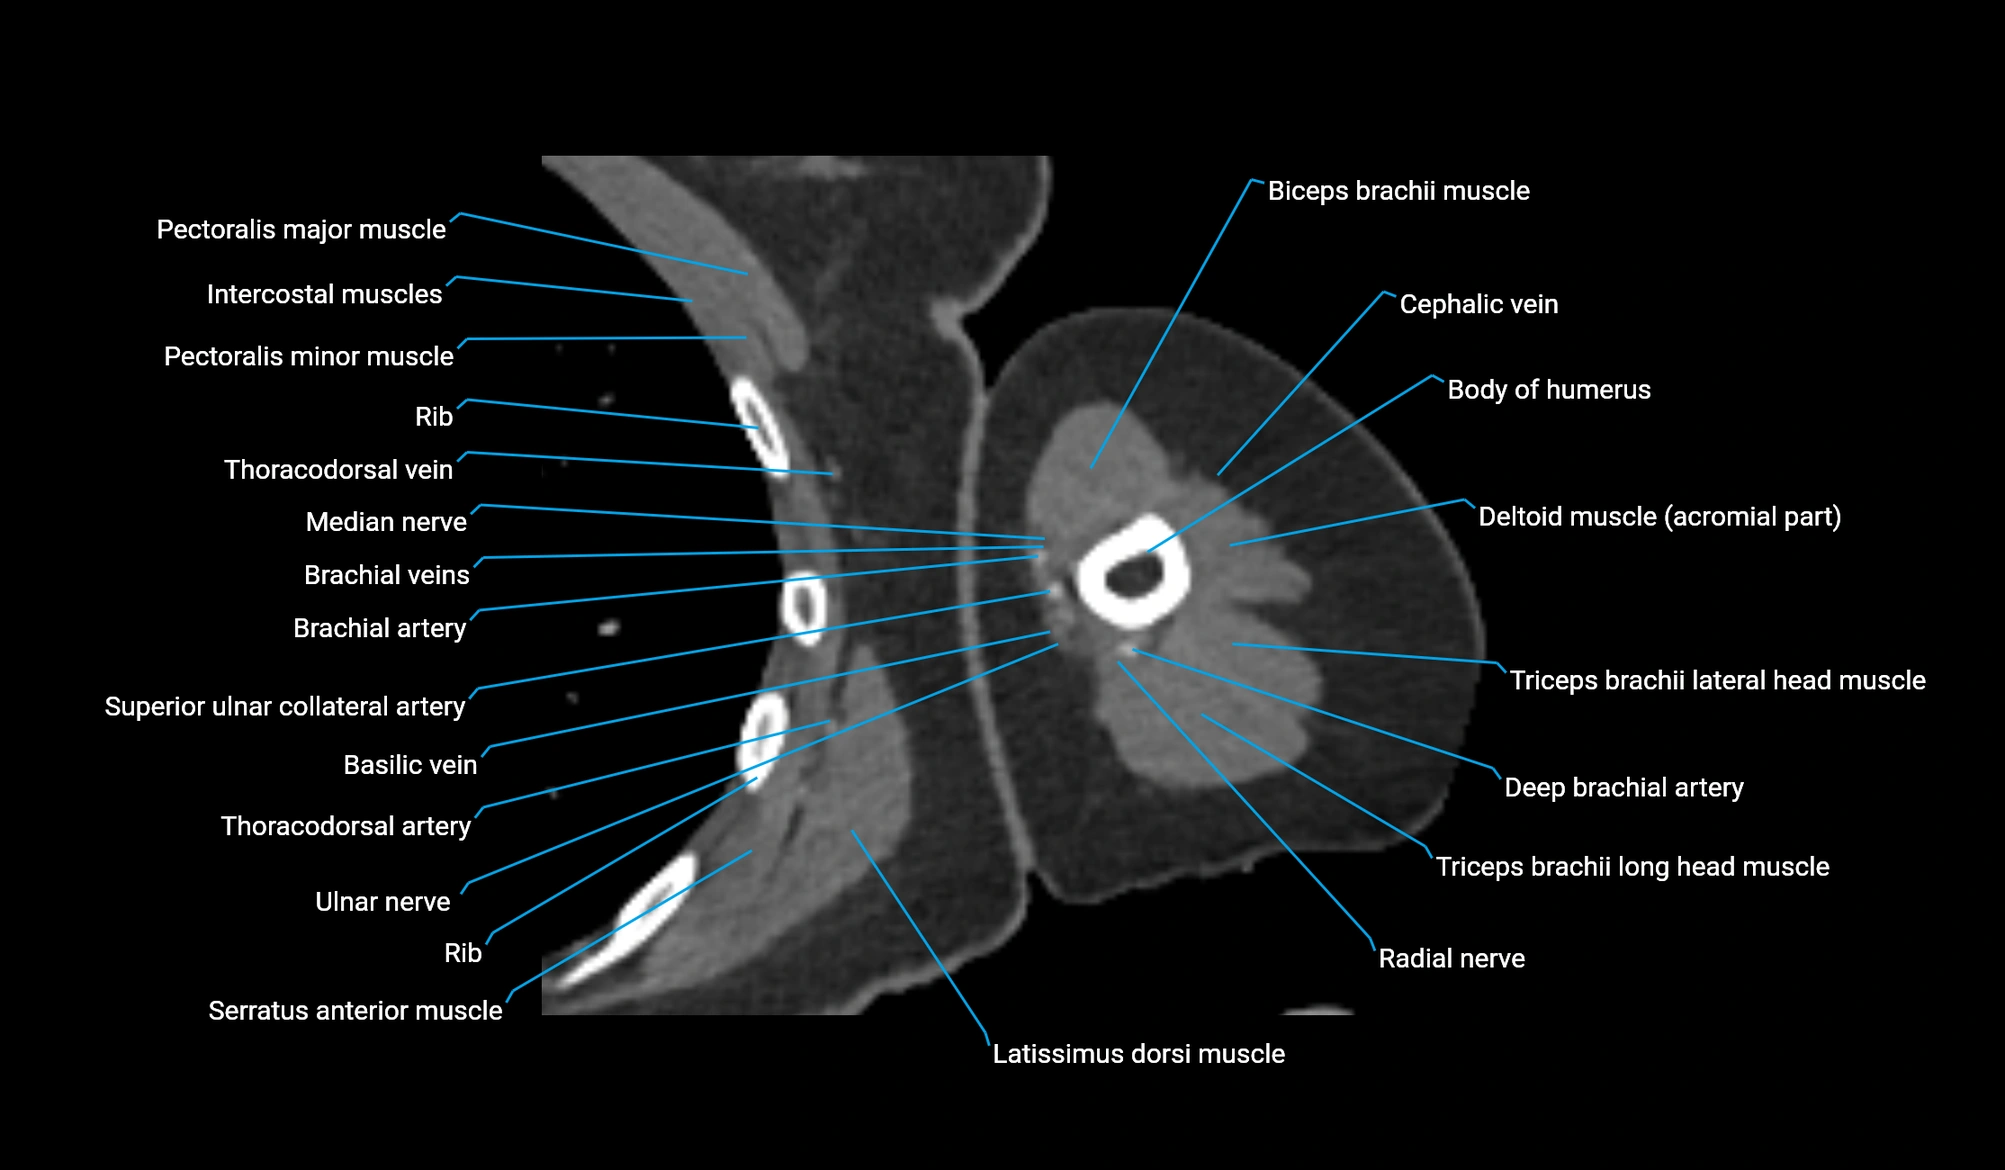

- Basilic vein

- Brachial artery

- Brachialis muscle

- Deep brachial artery

- Long head of triceps brachii muscle

- Median nerve

- Radial nerve

- Superior ulnar collateral artery

- Thoracodorsal artery

- Ulnar nerve